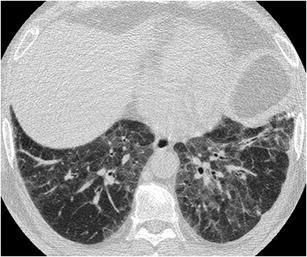

Upper lobe predominant centrilobular ground glass, OR prominent mosaic pattern

Hypersensitivity Pneumonitis

(subacute)

lobular GGO

Need constellation of findings to dx: exposure to an offending antigen, characteristic signs and symptoms, abnormal chest findings on physical examination, and abnormalities on pulmonary function tests and imaging